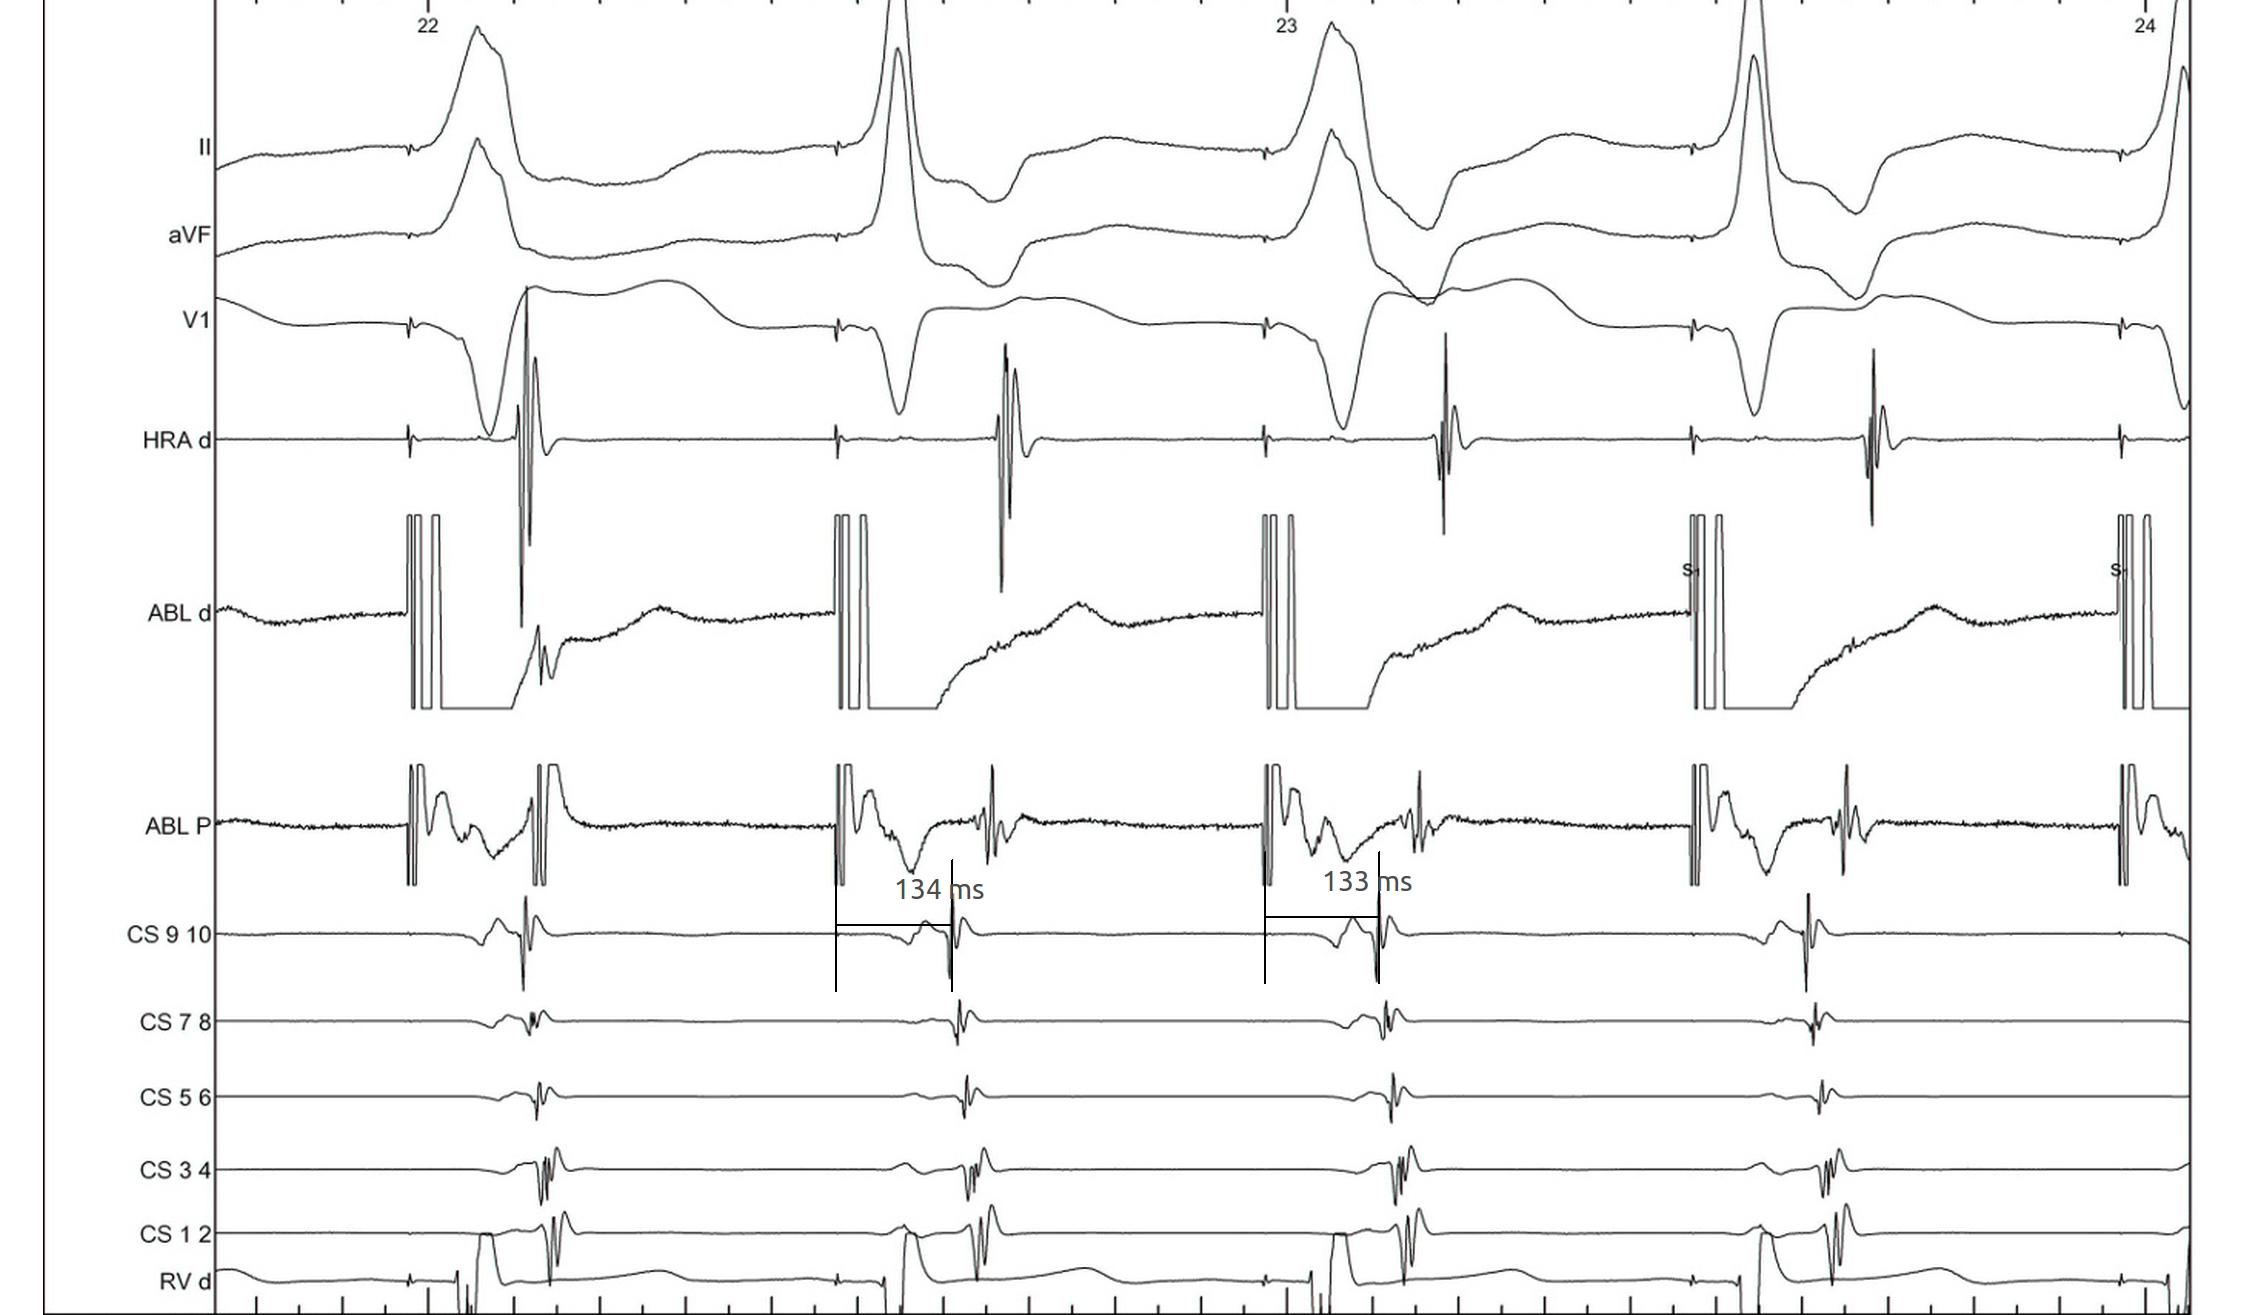

Bundle branch block

lbbb_narrow.jpg

lbbb_narrow_measurements.jpg

coumel.jpg